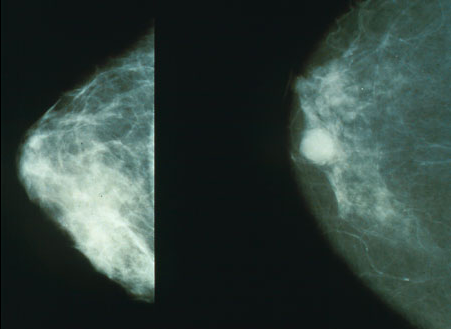

Higher susceptibility to breast cancer has been found in many studies of rodents and primates exposed to BPA.[63] However, it is the impact BPA has on breast cancer development in humans is unclear, as it is difficult to quantify an individual's BPA exposure over their lifetime.[63] BPA, which includes a phenolic structure, has shown an association with agonist and antagonistic endocrine receptors that facilitate endocrine disorders such as breast and prostate cancer. Other endocrine disorders include infertility, polycystic ovary syndrome, and precocious puberty.[64][65]

More oxidative stress in breast cancer cells were found to be directly proportional to BPA exposure as per the findings in several In vitro studies.[61] Additionally, work related exposure to BPA, and women who are postmenopausal have suggested an increase in breast cancer incidence.[66][67]